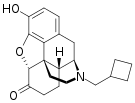

Others

- 1-Nitroaknadinine * 14-episinomenine

- 5,6-Dihydronorsalutaridine

- 6-Keto Nalbuphine

- Aknadinine

- Butorphanol

- Cephakicine

- Cephasamine

- Cyprodime

- Drotebanol

- Fenfangjine G

- Ketorfanol

- Nalbuphine

- Nalbuphone

- Tannagine

Structures

| Other Morphinans | ||||

|---|---|---|---|---|

1-Nitroaknadinine 1-Nitroaknadinine |

14-episinomenine 14-episinomenine |

5,6-Dihydronorsalutaridine 5,6-Dihydronorsalutaridine |

6-Keto Nalbuphine 6-Keto Nalbuphine |

Aknadinine Aknadinine |

Butorphanol Butorphanol |

Cephakicine Cephakicine |

Cephasamine Cephasamine |

Cyprodime Cyprodime |

Drotebanol Drotebanol |

Fenfangjine G Fenfangjine G |

Nalbuphine Nalbuphine |

Sinococuline Sinococuline |

Sinomenine Sinomenine |

Tannagine Tannagine |